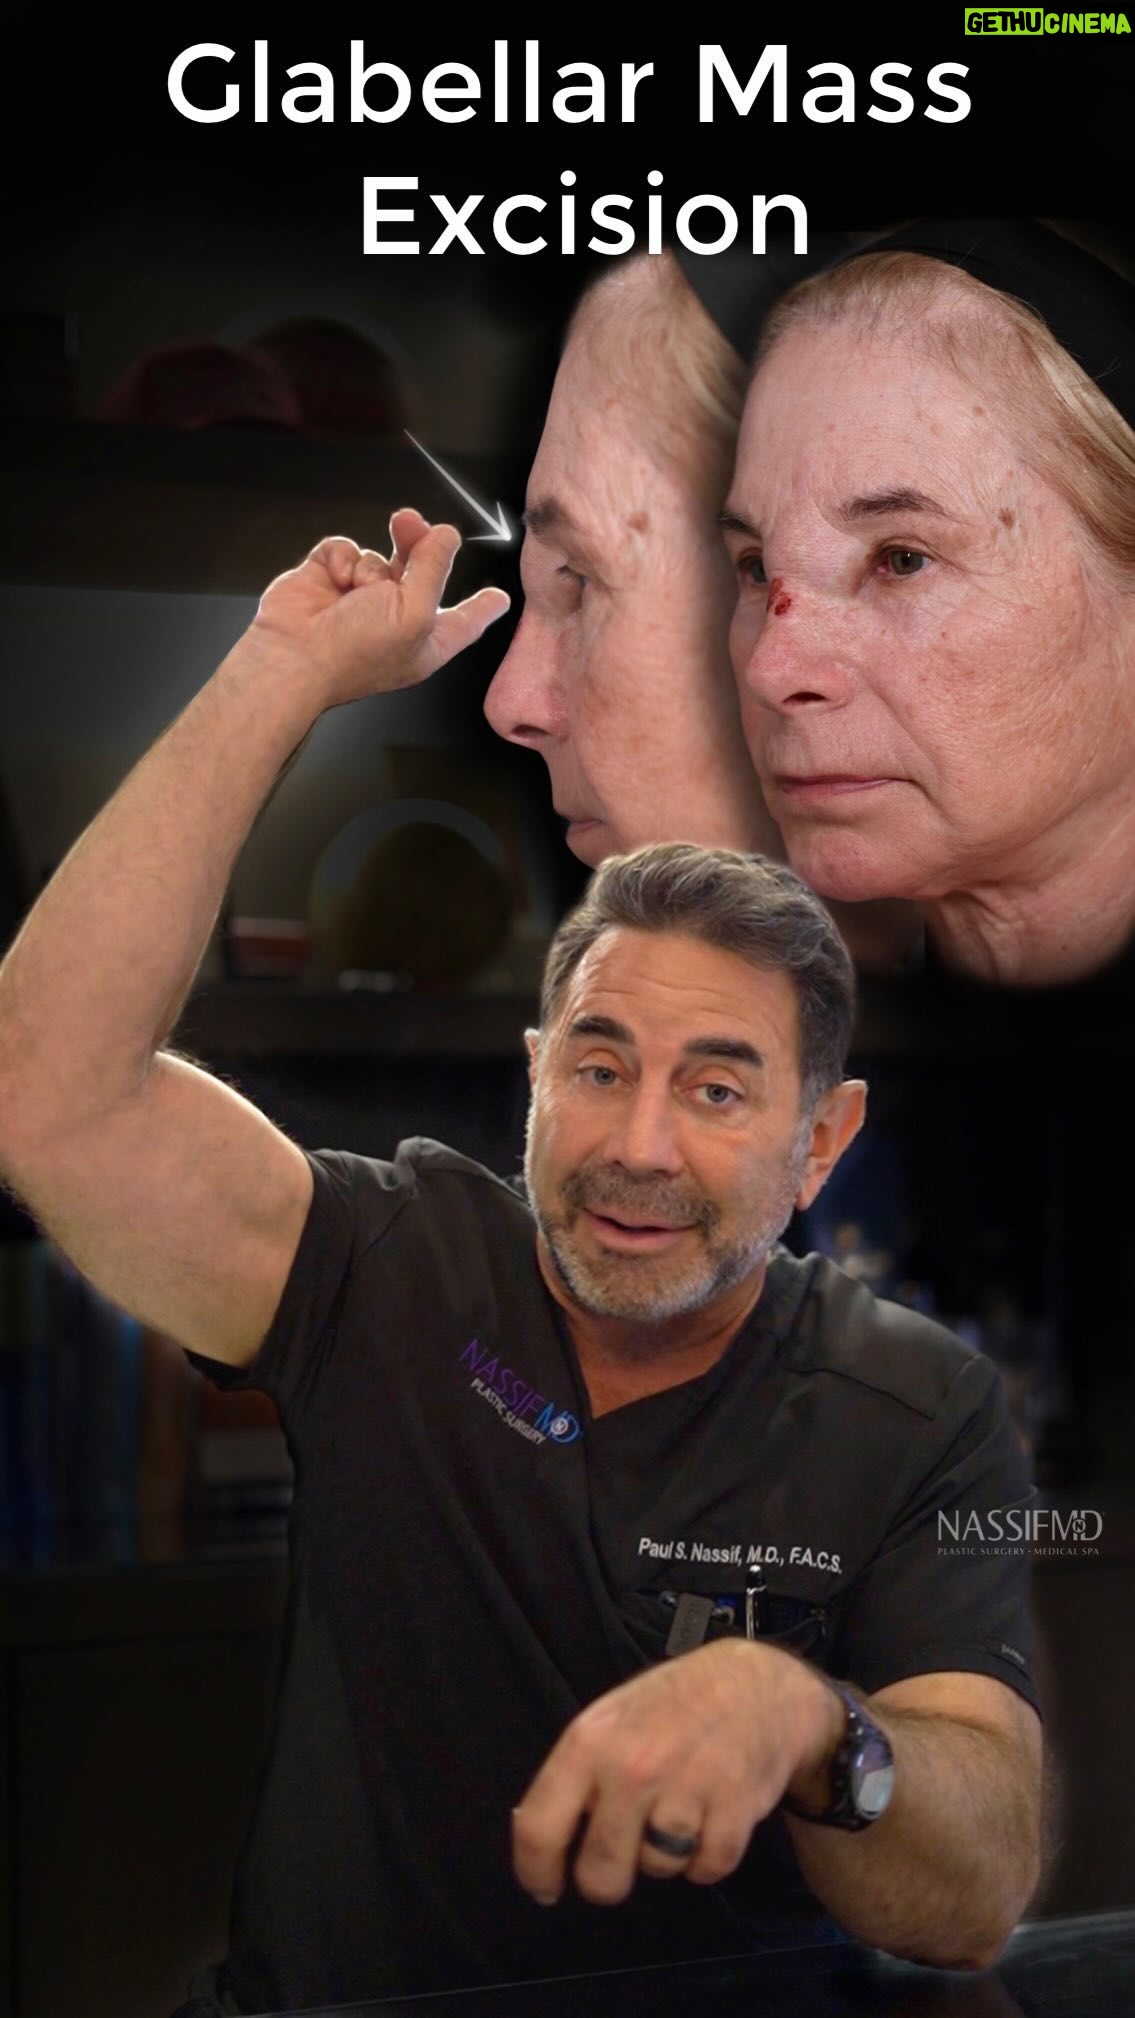

8.2K Likes – Paul Nassif Instagram

Caption : ⚠️ Warning: Do Not Inject Filler Into Your Glabella! Not only can it cause skin necrosis, which means the skin dies, but it can even cause blindness or other problems. My patient, Linda, developed this big mass, which you can see in the video above. FDA approved filler doesn’t usually cause this type of reaction, so we didn’t exactly know what was going on until we went into the OR. By doing a modified Lynch procedure, where we made incisions on the sides of the nose and dissected out the mass of tissue, we figured out what it was. The tissue ended up being what we call a foreign body reaction. Her body created the mass because it didn’t accept whatever was injected into her face. Here are Linda’s results after only 1-month, but they’ll continue to improve as swelling will decrease over the next three to four months! If you would like to treat the glabella, @nassifmedical recommends using Botox or a laser treatment instead! Trusted with Faces Worldwide® _____________________________________________ ☎️☎️ Call us at: 1 (310) 275-2467 💌💌 Email us at: [email protected] #nassifmedical #nassifmd #filler #botched #botchedfiller #glabella #facialplasticsurgery #beforeandafter #results #modifiedlynchprocedure #plasticsurgeon #cosmeticsurgery #facialplasticsurgery #face #tt #transformationtuesdayLikes : 8173